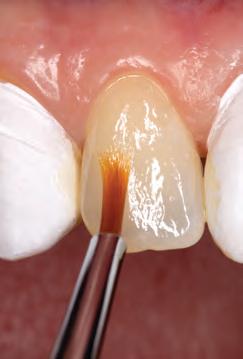

Techniques

Free-hand: This technique involves the addition of composite layers without the use of any matrix or containing system.23 It relies on the dentist’s ability to manipulate the material in a cavity preparation or to address various issues, such as replacing missing dental tissue in an incisal edge, repairing enamel defects, closing diastemas, or filling small cavity preparations.13,16 Practitioners may choose between different viscosities of resin composite, some opting for flowable or less viscous materials and some preferring higher viscosity, such as conventional composites.5,13 Instrumentation varies from using just the tip of the flowable material to injecting and smoothing thin-bladed instruments and brushes for conventional materials.3 (Fig. 2)

For most free-hand techniques, a conventional mylar strip is necessary.3,24 These strips aid in composite placement and the common “pull-through” technique,3,25 which involves pulling material through the interproximal with the mylar strip to fill proximal areas. While effective in skilled hands, this technique can be challenging and impractical for novices.24 Furthermore, it only works when utilizing very “waxy,” nonsticky, firm materials and is contraindicated for flowable and sticky materials.26

Direct technique with customized prefabricated palatal guides: This technique requires pre-operative impressions of both arches using polyvinyl siloxane (PVS) to prepare a dental cast and transfer the proposed changes from the wax-up.4 (Fig. 5) The palatal index, which is an impression of the palatal portion of the tooth or teeth to be restored, is created using a PVS impression material21 or laboratory silicone.4 During the restorative phase, the index is seated on the palatal side after placing the adhesive. The composite is placed onto the silicone guide to form the restoration’s palatal aspect (palatal/proximal contour and incisal edge).9,10 Once this palatal increment is light-cured, the silicone matrix is removed, and the remaining part of the restoration can be incrementally built up with resin composite.21 A monochromatic material can be used to build the remaining of the restoration, or it can be incrementally built with various opacities and chromaticities to imitate dentin and enamel using “dentin- and enamel-like” materials or by adding layers of translucent composite between the lobes.10 Ultimately, each patient is unique when it comes to selecting the right enamel shade for the final layer.6,10

Advantages of this technique include minimal finishing and polishing of the palatal portion and occlusal adjustments because all details were worked out during the wax-up phase before the matrix fabrication.4,32 The first palatal increment provides a canvas where the dentist can add

the remaining increments to build the restoration.4,10 This technique is beneficial when multiple restorations are to be placed and when the length of the teeth is going to be increased. Thus, the anterior guidance is dialled in the waxup.4,32 Disadvantages include an additional or a longer appointment for impression and laboratory work waxing for future restoration or restorations.32 A longer appointment is required if a polychromatic restoration is to be placed.10 This technique still relies on the ability and skill of the dentist to layer composite and to properly replicate anatomical contours as contouring and polishing.9,10